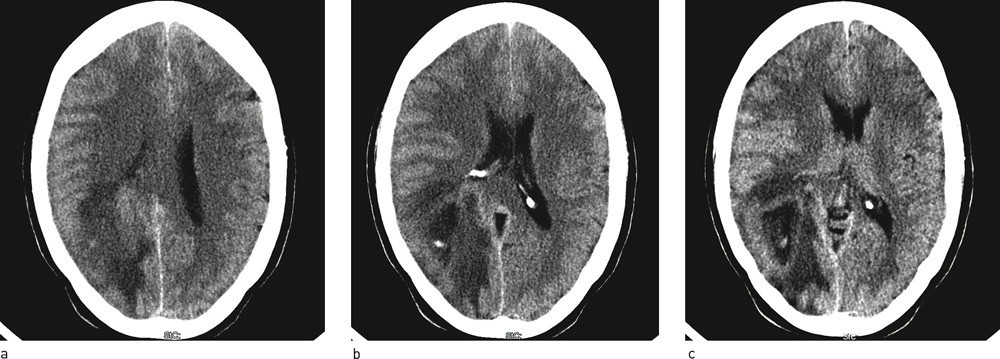

Ved 14-tiden ti dager etter symptomdebut ble det utført en CT caput uten kontrast. Det ble funnet høyresidige parietallappsforandringer med perifokale, vasogene, ødematøse forandringer (fig 1 a – c). Hun ble så innlagt i nevrologisk avdeling ved sentralsykehus for videre utredning og tiltak. Pasienten ble tatt imot i akuttmottaket rundt 17-tiden samme dag og var ved innleggelse lite plaget av hodepine. Den ble beskrevet som moderat, trykkende og pressende av karakter med global utbredelse, men mest uttalt i begge tinningregioner. Ut ifra opplysninger gitt i anamnesen hadde hun vært plaget med intermitterende kvalme og brekninger, slapphet, fatigue og dissosiativ følelse der hun hadde følt seg «utenfor seg selv». Hun benektet synsforstyrrelser, svimmelhet, nakkestivhet og lysskyhet. Opplysninger gitt av pårørende avslørte at pasienten hadde hatt atferdsforandringer. Ved noen anledninger hadde hun gått på dører, vært fjern, hatt usammenhengende tale og enkelte ganger ikke gitt god kontakt ved tiltale. Ved påkledning hadde hun blant annet tatt på buksene bak-frem.

CT-undersøkelsen tatt rett før innleggelse viste en hypodens lesjon parietooksipitalt på høyre side og betydelig perifokalt, vasogent ødem med noe midtlinjeforskyvning. Det var gode plassforhold basalt i kraniet rundt hjernestammen og i de basale cisternerom. Bildefunnet kunne forklare hodepinen, de nevrologiske utfallene med venstresidig hemianopsi, redusert tempo og finmotorikk i venstre hånd og atferdsforandringene de siste dagene før innleggelsen. I vår første bedømmelse av CT-bildene konkluderte vi med forandringer mer typisk for en intrakranial neoplastisk lesjon som for eksempel høygradig gliom eller metastasering fra cancer annet sted. Etter metastaser er høygradige maligne svulster som glioblastom (glioblastoma multiforme) den hyppigste intracerebrale svulsttypen i den voksne befolkningen (3).

Den første CT-undersøkelsen ble gjort før innleggelse i sykehus og var etter standardprotokoll uten kontrast (fig 1). Undersøkelsen viste en lesjon der videre bildediagnostikk var nødvendig. Hvorfor det ikke umiddelbart ble utført CT-undersøkelse med kontrast av henvisende instans utenfor sykehuset da primærundersøkelsen viste tydelige forandringer, er uvisst. En slik undersøkelse ville ha fremskyndet diagnostiseringen og dermed behandlingen, som videre kunne ha endret prognosen. Ved CT-undersøkelse med kontrast vil abscesser oftest vise seg som ringoppladende lesjoner som et tegn på at blod-hjerne-barrieren er brutt og at det foregår en aktiv prosess rundt pusslommen. For å kunne skille abscesser fra andre intrakraniale romoppfyllende prosesser som høygradige maligne svulster er MR-undersøkelse med og uten kontrastserier, diffusjonsvektede sekvenser og spektroskopi en forutsetning for riktig diagnostikk (8).